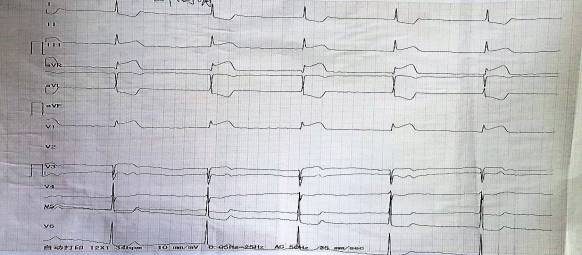

入院心电图: 窦性心律。

术后心电图: